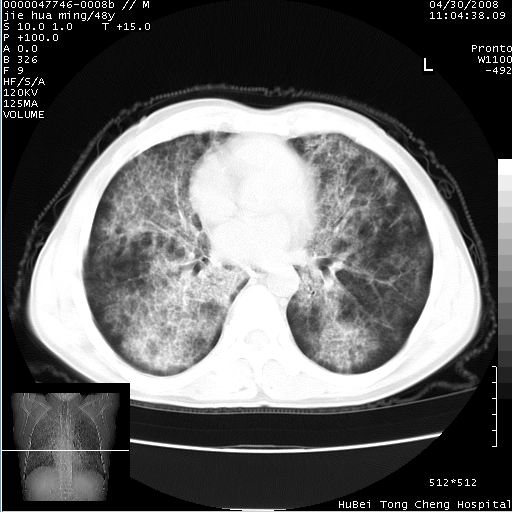

以下是引用dr.yang在2008-5-1 6:25:00的发言:[br]两肺广泛毛玻璃样的片状影,密度不均,边缘欠清,呈碎石路样改变,[br]考虑,1双肺间质性肺炎,2肺泡蛋白沉积症3支气管肺泡癌[br]

以下是引用hhcckk在2008-5-1 8:06:00的发言:[br]支持肺泡蛋白沉积症[br]依据:[br]1、病灶边缘清楚----地图征[br]2、病灶内部小叶间隔或小叶内间隔增厚所形成的网格状影----碎石路样表现[br]3、抗炎治疗无效(炎症抗炎治疗有效)[br]4、纵隔内未见肿大淋巴结(肺泡细胞癌时常有)[br][br]附肺泡蛋白沉积症资料[br][br]肺泡蛋白沉积症(pulmonary alveolar proteinosis)是一种原因不明的以肺泡腔内大量含脂糖蛋白样物质沉积为特征的疾病。[br]病理改变:(1)肺泡和细支气管腔内充满大量含脂糖蛋白样的粘稠物质,该物质为颗粒状或絮状的糖原pas染色阳性的磷脂蛋白。(2)肺泡壁及其间隔无异常改变。胸膜和淋巴结不受累及。(3)晚期可出现弥漫性肺间质纤维化。[br]临床表现:(1)好发年龄30~50岁,男性多于女性,偶见于儿童;(2)主要症状为呼吸困难、咳嗽、低热、消瘦、低氧血症和杵状指等。1/3的患者无症状。(3)实验室检查:痰液或肺泡灌洗液中可找到pas染色阳性颗粒物质。[br]hrct表现:肺泡蛋白沉积症具有特征性改变,即“碎石路样”表现(crazy-paving appearance,cpa)。主要包括(1)斑片状磨玻璃影:指肺野密度朦胧增加,内可见肺血管纹理影,系肺泡腔内充满低密度的磷脂蛋白物质所致。(2)其内部小叶间隔或小叶内间隔增厚所形成的网格状影,为小叶间隔水肿、肺泡壁内淋巴细胞和巨噬细胞浸润以及小叶内淋巴管扩张的缘故。(3)病灶边缘清楚,呈地图样分布于肺野外围或肺门及中央区。[br]

以下是引用zsl6918在2008-5-1 7:35:00的发言:[br]双肺磨玻璃样病变,可见铺碎路石征,病变区与正常区交错。边界清晰。符合肺泡蛋白质沉着征,高分辨扫描会更清楚漂亮。建议临床肺泡灌洗。

以下是引用yangyudong333在2008-5-1 5:36:00的发言:[br][br] 两肺广泛毛玻璃样的片状影,密度不均,边缘欠清,呈碎石路样改变,[br]考虑,1双肺间质性肺炎,2肺泡蛋白沉积症[br]